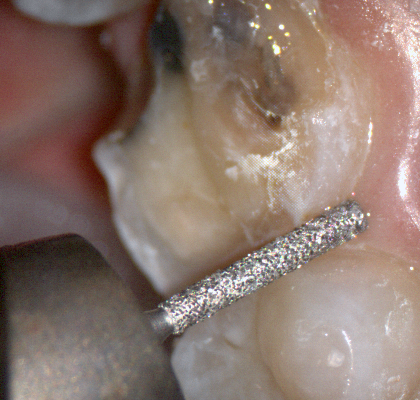

The following pictures depict the sequence of burs we recommend that you use to finish a preparation quickly. While patient is getting numb, take a quick look at the clearance you will need to reach proper material thickness. Once the quadrant is isolated with isolite and optragate, take an occlusal router bur and create a trough to gain the proper depth. Follow that with a flat disk, and you can quickly reduce the occlusal height.

A shoulder bur of .8 mm thickness can help you reduce the interproximal areas as well as the buccal and lingual margin lines. Before finishing the prep, place hemostatic agent like expasyl in the sulcus and place retraction cord. while it is setting, check your reduction. If you need more space, now is the time to reduce some more.